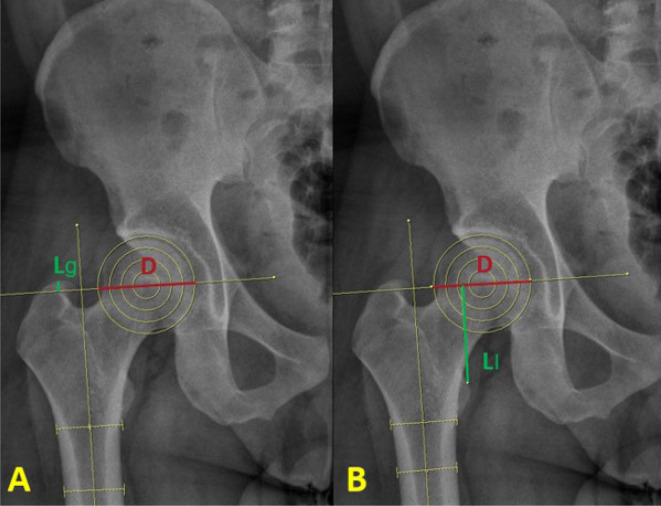

Purpose: The objective of the current study is to introduce a proposed method and evaluate its efficacy using the greater trochanter (GT) tip rather than the lesser trochanter (LT) as an anatomical landmark to reduce leg length discrepancy (LLD) during performance of hip arthroplasty.

Materials and methods: Thirty-two patients who underwent hip arthroplasty were divided according to the GT group (n=17) and the LT control group (n=11); four patients were excluded. LLD was determined by assessing the vertical lengths parallel to the line connecting the lower margin of the teardrop to the most prominent part of the LT on a standing anteroposterior pelvic X-ray taken 30 days after the procedure. The mean and median LLD of the two groups were compared. Analysis of planning for femoral stem depth insertion and postoperative results was also performed.